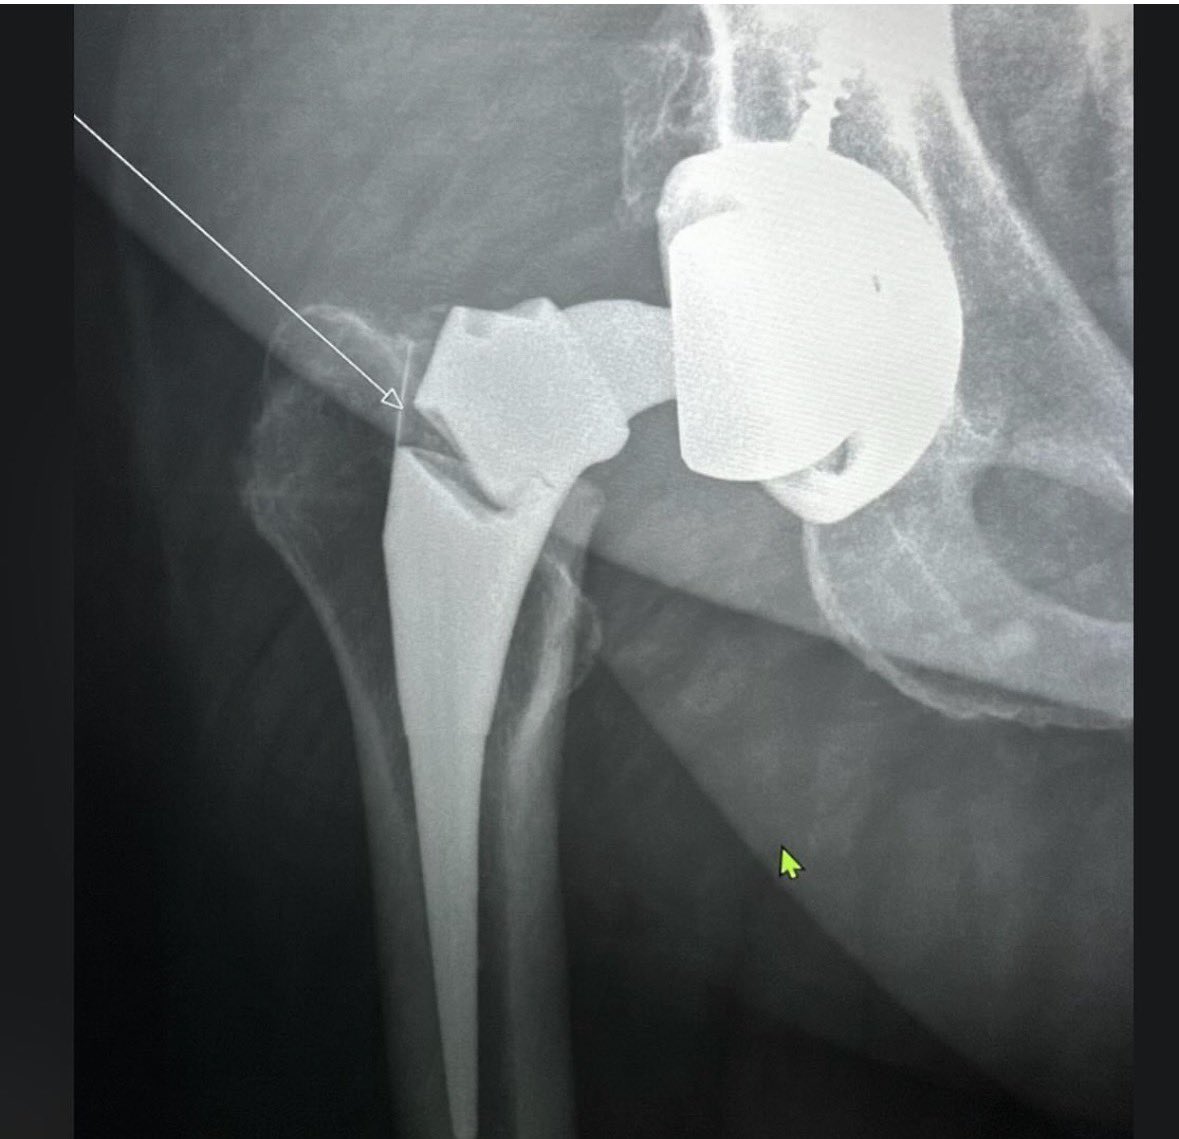

@generalorthomd @jointdocShields @schulte_ss @NaanDerthaal @ChrisGraysonMD1 @tbclay @aschwartz45 surgeon error… and by “error” I mean not having a multi billion dollar company who can move the goal post.